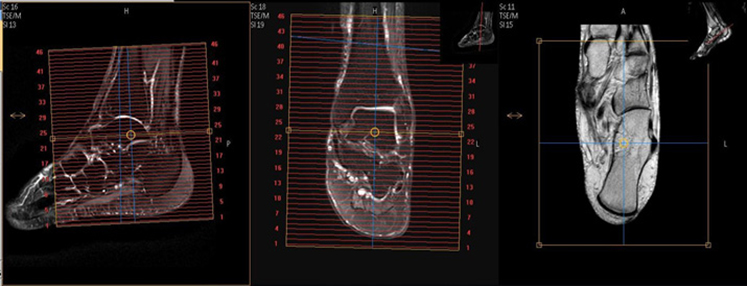

Angle to Tib/Fib (Ankle Protocol)

| AXIAL | T1 | TSE | 3mm | 0.3mm | None | 15cm | Cover thru Metatarsal Bases (as below) |

| AXIAL | T2 SPAIR | TSE | 3mm | 0.3mm | SPAIR | 15cm | Cover through metatarsal bases |

| SAG | T2 STIR | TSE | 3mm | 0.3mm | STIR | 15cm | Angle to Calcaneus |

| SAG | T1 | TSE | 3mm | 0.3mm | None | 15cm | Angle to Calcaneus |

| COR | T1 | TSE | 3mm | 0.3mm | None | 15cm | Perpendicular to Axial |

| COR | T2 SPAIR (run as STIR for infection) | TSE | 3mm | 0.3mm | SPAIR (or STIR) | 15cm | Perpendicular to Axial |